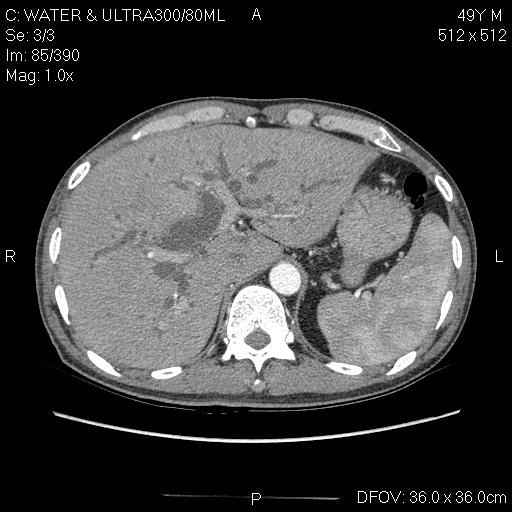

CT-u đầu tụy